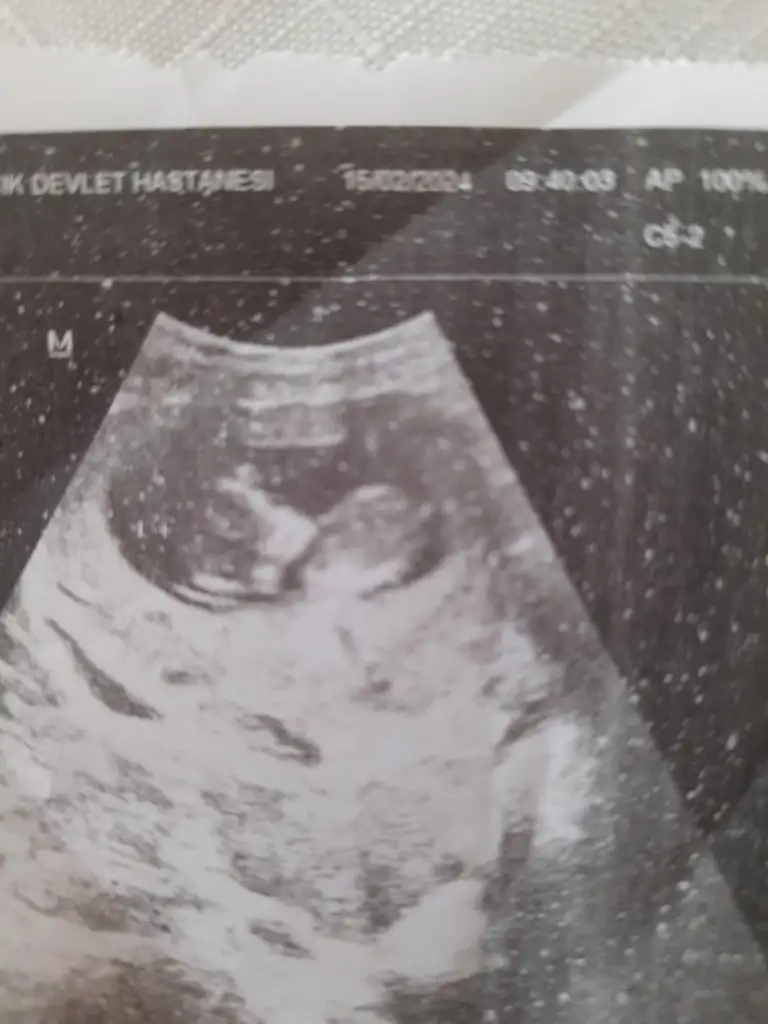

Vajinal ultrason bana da bakar mısınız lutfenYerleşim yeri erkek ama kemik yapısı kız. Bence minnoş bir kız olacak6-7 haftalık usg görüntüsü varsa ona da yorum y

Kızlar bugün kontrolüm vardı şuan 12.haftamın içindeyim 2 li tarama yapıldı ama cinsiyetine erken olduğu için doktor bir şey demedi. Bir ay sonraya çağırdı gerçekten merak ediyorum tecrübeli olanlar varsa tahmin edebilir miBi de 2 gün geç döllenme olmuştu başta ama şuan 1 gün önden gidiyormuş belki işinize bana da yorum yaparmisiniz bende çok merak ediyorum

Bana da yorum yaparmisiniz bende çok merak ediyorumKızlar bugün kontrolüm vardı şuan 12.haftamın içindeyim 2 li tarama yapıldı ama cinsiyetine erken olduğu için doktor bir şey demedi. Bir ay sonraya çağırdı gerçekten merak ediyorum tecrübeli olanlar varsa tahmin edebilir miBi de 2 gün geç döllenme olmuştu başta ama şuan 1 gün önden gidiyormuş belki işinize yarar